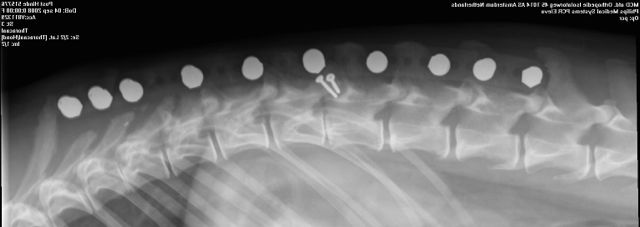

Hinde’s nacontrole in Amsterdam 08 zaterdag nov 2014 Originele grootte op 640 × 227 ≈ Een reactie plaatsen